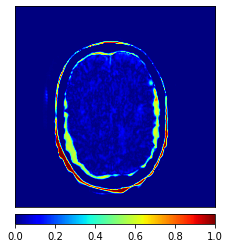

Moreover, Figs. 6 and 7 show the synthesized MR and CT images along with the errors between the real and synthesized images by different methods, respectively. It can be seen that the synthesized images by DC-cycleGAN are more identical to the real ones as compared with other methods. This indicates that effectiveness of SSIM and CE along with dual contrast in synthesizing images. In addition, the error between the groundtruth and synthesized MR/CT images by DC-cycleGAN is relatively less as compared with other methods.